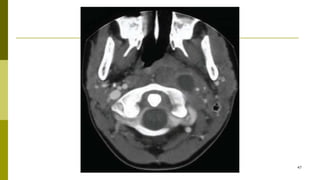

□ For patients in whom acute tonsillitis is suspected to have

□ In cases of PTA, CT scanning with contrast is indicated 43

□Routine imaging is not useful in cases of acute

□Peritonsilar abscess CT scan with contrast

□CTscan may be used to guide needle

aspiration for draining PTA.